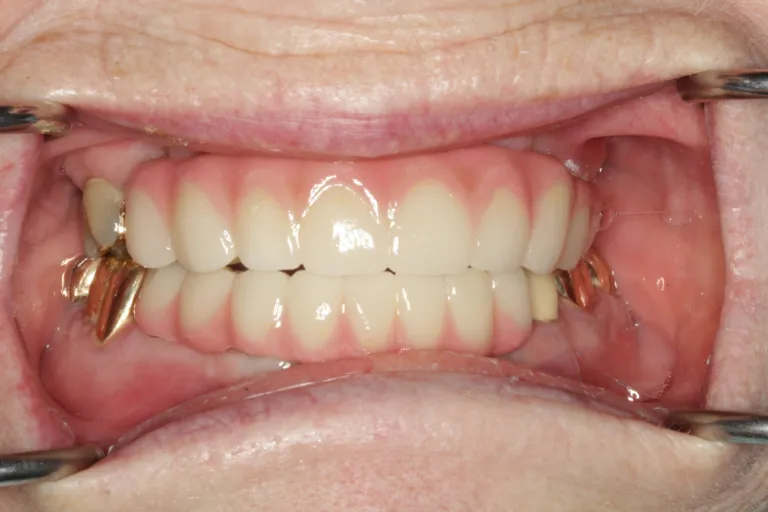

Full Mouth Reconstruction with Fixed Implant Bridge – All on X

IMPrESS Perio Implant Center Dr. Noroozi Vancouver Periodontist Implant Specialist Burnaby BC